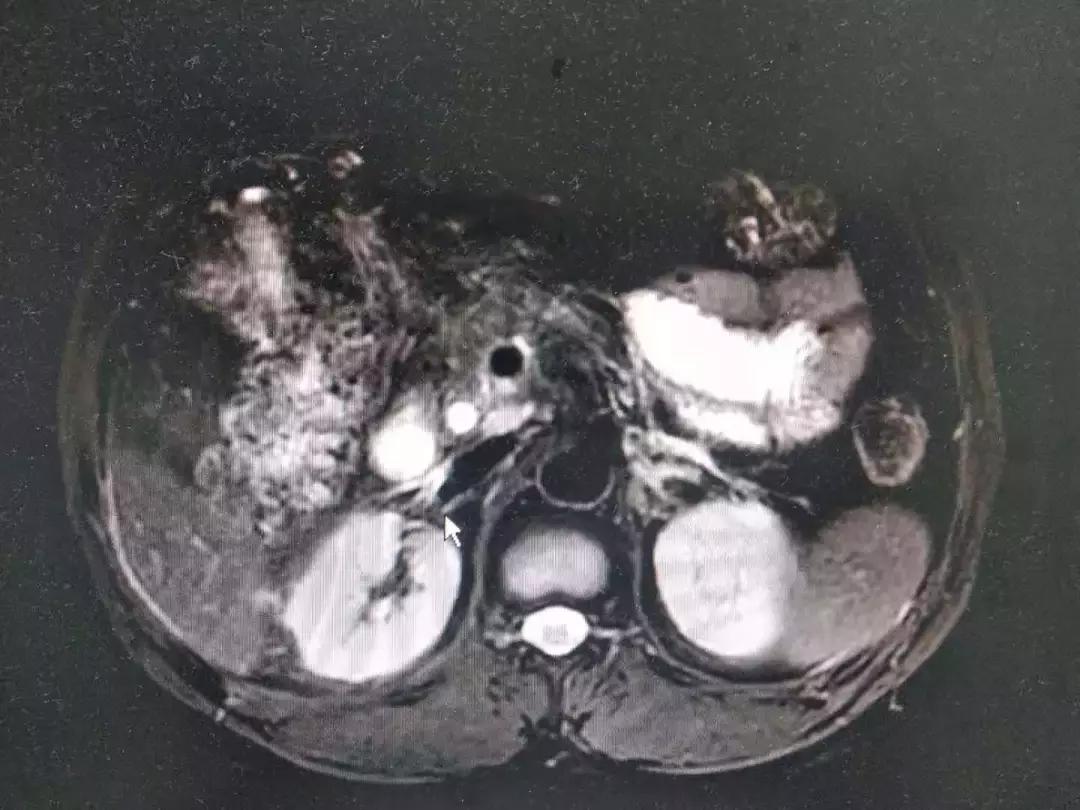

患者因持续上腹疼痛伴高热黄疸1天入院,患者1天前因上腹痛伴发热在其他医院就诊,查腹部CT提示胆囊结石,胆囊炎,胆总管结石,胆总管扩张,并出现黄疸,患者未行手术治疗,腹痛黄疸发热加重,后就诊于我院。入院后,普外科在左富义主任团队的带领下详细询问病史,完善MRCP检查,发现胆总管多发结石引起急性梗阻性化脓性胆管炎,梗阻性黄疸,需急诊手术治疗解除胆道梗阻,左主任组织科内进行术前讨论,充分完善术前准备,术前给予补充维生素、改善凝血功能,抗炎营养支持等治疗。于8月21日在左富义主任指导下,由石世华副主任、张锦秀副主任医师及张芮浦医师在气管插管全麻下实施腹腔镜、胆道镜联合胆总管切开探查取石、胆囊切除、T管引流术,手术顺利,术后给予抗炎、营养支持、中药导入、保肝退黄等治疗,患者术后次日恢复饮食,T管引流通畅,腹腔引流管已拔除,体温及肝功能恢复正常,痊愈出院。

胆总管结石是临床常见疾病,病情通常变化快,常引起肝功能进行性损害及急性梗阻性化脓性胆管炎,后期可引起感染性休克、肝脓肿、肝功能衰竭危及患者生命,需要限期甚至急诊进行手术治疗,有效解除梗阻,方可改善肝功能、凝血功能,感染多能在梗阻解除后得到有效控制。因结石梗阻部位特殊,目前手术治疗方案有开腹胆总管切开探查取石、胆囊切除、T管引流,ERCP检查十二指肠乳头切开取石(EST)、鼻胆管引流术(ENBD),然后再行胆囊切除术,此外还可行腹腔镜联合胆道镜胆总管切开探查取石,胆囊切除术。开腹手术创伤较大,住院时间长,需要较长时间留置T管;ERCP内镜下行EST取石有手术成功率不高以及取石术后继发反流性胆管炎及十二指肠乳头因切开后导致狭窄等远期并发症,治疗费用昂贵,普及率不高。